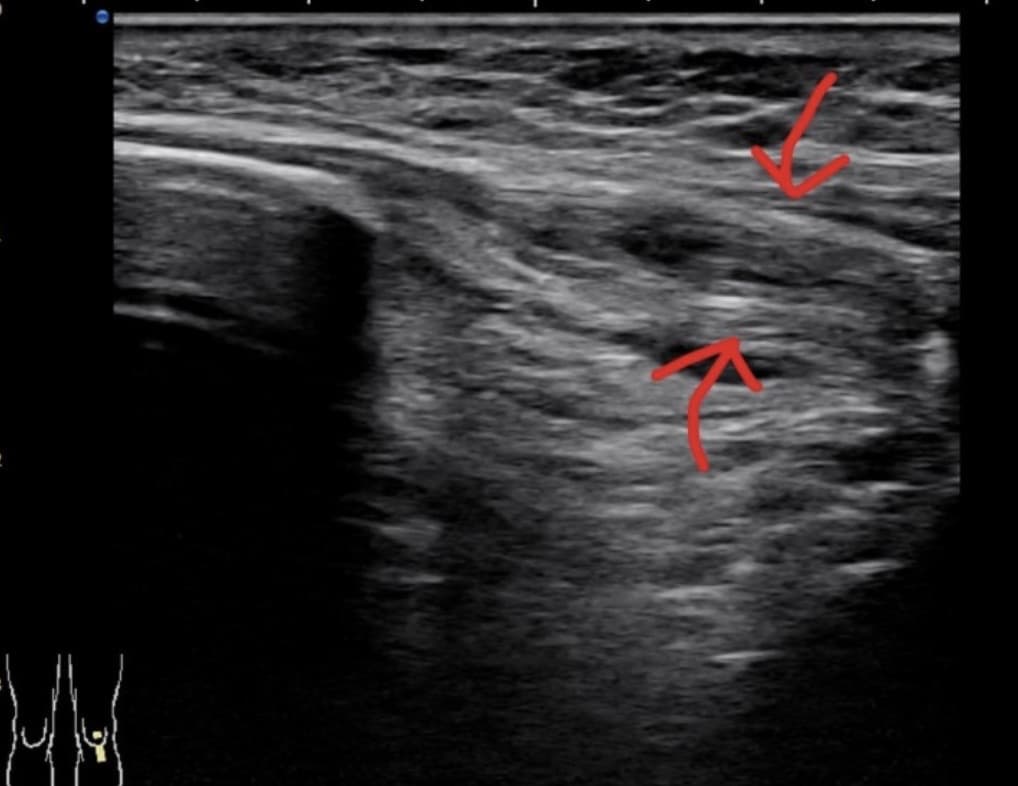

근육의 감염은 처음에는 불균질한 에코가 주위와 구별이 잘 안 되어 불분명하게 보이다가, 이후에는 고름집(농양)을 만드는데, 고름집은 낮은 에코 또는 에코 없는 낭성종괴로 보인다. 드물게 고름집이 주변조직과 같은 에코 또는 높은 에코를 보여서 찾기 어려울 수 있다. 농양(abscess) 뒤쪽에 '메아리투과증가'(through-transmission)에 의한 높은 에코를 보이며, 탐촉자로 압력을 가할 때 내부 에코의 소용돌이 또는 회오리현상(swirling)을 봄으로써 내부에 액성물질(fluid component)이 있음을 알 수 있다.

영상 영역(field-of-view)을 크게 하여 농양 주위를 넓게 보면, 농양 뒤쪽의 메아리투과증가를 좀 더 쉽게 볼 수 있다. 수술후 환자에서 농양이 금속물에 가까이 있을 수 있다. 화농성윤활주머니염은 이미 알려진 윤활주머니의 위치에서 내부에 다양한 액성에코와 윤활 막 증식을 보인다. 연조직 감염이 공기를 가질 수 있으며, 공기는 작고 높은 에코의 점상으로 보이며, 그 뒤쪽에 혜성꼬리허상(comet-tail artifact)을 가진다. 연조직 감염이 발견될 때, 가까이 있는 뼈까짐, 파괴 등으로 뼈 표면이 불규칙해지면 골수염을 생각해야 한다.